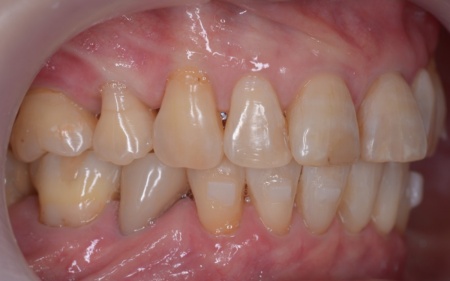

- 年齢・性別 60代女性

- 診療種別 自由診療

- 治療期間の目安 1年3ヶ月

- 治療費総額の目安 1,100,000円